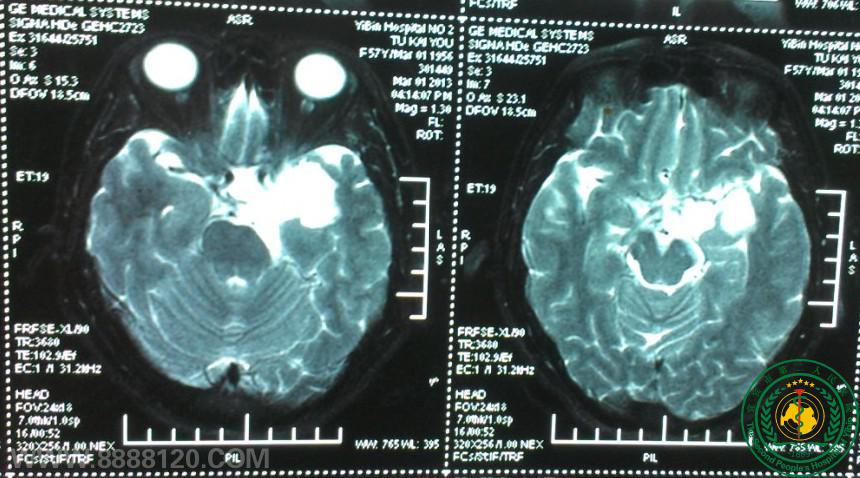

我科顺利完成颅内毗邻脑干肿瘤切除术一例

我科顺利完成颅内毗邻脑干肿瘤切除术一例5902